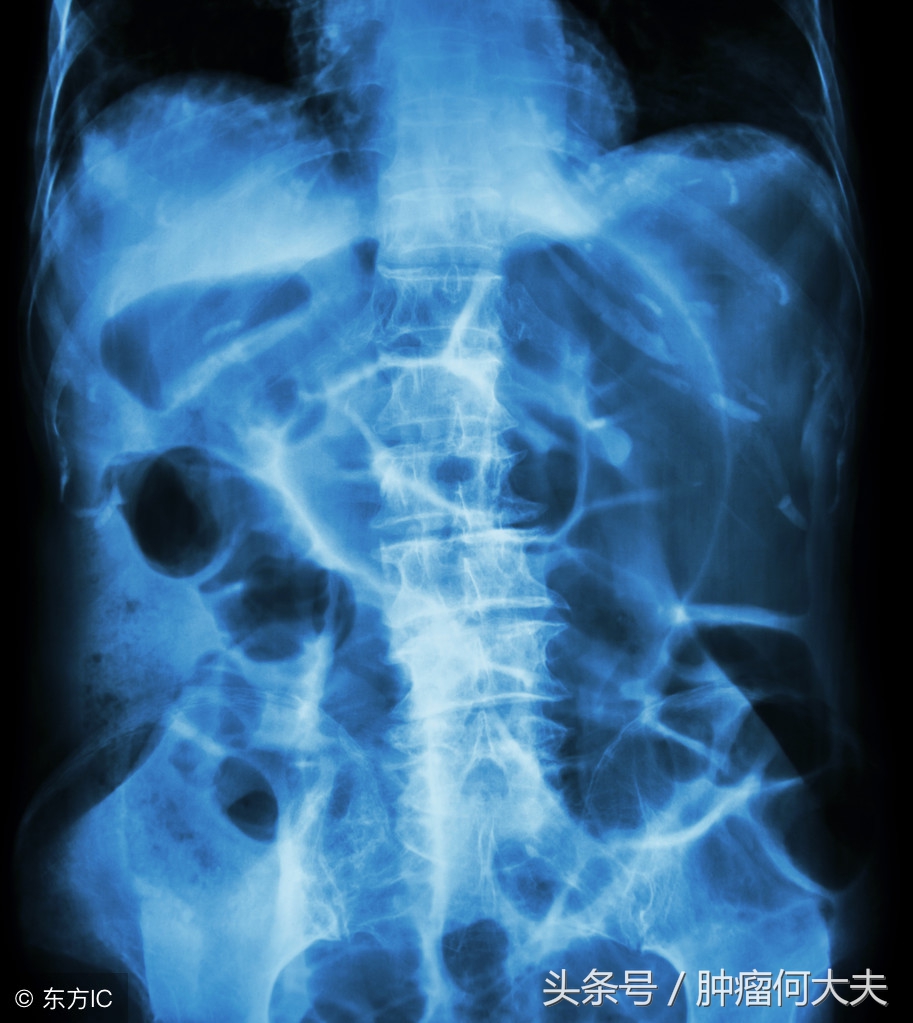

术后王先生恢复期一直很长,食欲不振,伴乏力,腹胀,曾一度出现小肠梗阻,第一次梗阻是中午吃了还没有泡透发开的木耳,饭后约1个多小时就出现了轻度腹痛,未重视晚上还吃了一些面条,半夜腹部疼痛加剧并呕吐,于手术医院就医时被诊断为肠梗阻。医生下胃管,禁食,禁水,静脉补液以维持营养,口服石蜡油不久就排出一堆像煤渣一样的排泄物,肠子终于通了。

一周前王先生再次因腹胀伴发热,收住院,入院后化验检查提示①有感染,白血球偏高;②小肠梗阻,。造瘘袋每天有稀水样粪便排出,但量不多。在禁食,禁水,下胃管,负压引流同时,口服石蜡油,给予全肠外静脉营养支持,2天后患者腹胀未见明显缓解。后决定通过造瘘口处理,当时找了一根长约30厘米的尿管,后将尿管沿造瘘口插入,后用50ml注射器回抽,先抽出两管稀水样粪便,无明显臭味,抽第三管时候有阻力,后抽出小拇指大小的蔬菜叶团块(已经压缩在一起,但周围有菜叶样子,依然能看出它的原型),这个小蔬菜疙瘩被抽出后,哗哗的流出约有800ml稀便,而且粪水奇臭无比,此后患者腹胀明显好转,发热也逐渐好转。王先生回忆自己吃过炒空心菜。

肠癌病人,其中有不少都被迫造瘘,造瘘术后,大便改道不仅给患者带来生活上的麻烦,需要定期进行造瘘口袋清洁置换,而且有的患者由于造瘘口位置高,尤其是回肠造瘘,饮食不注意就会出现肠梗阻,弄不好也可能会致命。回肠造口是回肠末端在腹壁的开口。人体消化道的每一部分都发挥着重要的作用。食物在人的胃内形成食糜,在小肠内通过进一步消化,小肠能够吸收食物中绝大部分的营养,而结肠负责吸收水分,使便成形。回肠造口术后,消化的食物不再经过大肠,容易再经过腹壁的肠道时被截留,一旦发生这种情况,大概率就会阻塞。食物阻塞的结果就是,可能引起腹部痉挛,腹痛,腹泻等,饮食需要注意的是避免难以消化的食物,包括干果,椰子,红肉,菌类,空心菜,芹菜,豆角等食物。除饮食因素外,肠造口病人也要注意情绪因素,临床发现不少造口病人伴有抑郁症,抑郁状态会下调人体免疫力,导致病情复发。而开朗外向积极向上的精神状态有助于病情康复。